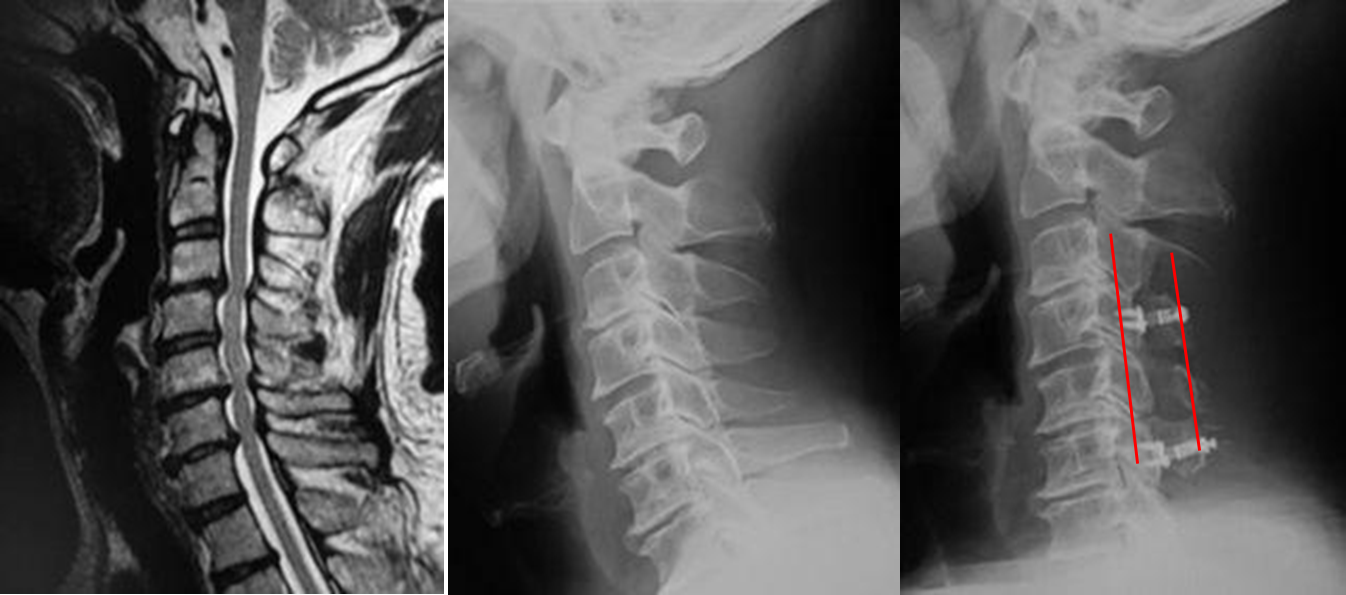

図 頚椎症性脊髄症

(左)術前MRI: 神経の通り道(脊柱管)が狭く、脊髄が圧迫されています。

(まん中)術前レントゲン:神経の通り道(脊柱菅)を赤線で示しています。

(右)術後レントゲン:神経の通り道(脊柱管)の赤線が

拡大しています。